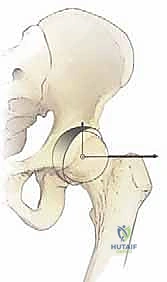

لفهم أهمية جراحة (PAO)، يجب أولاً فهم الميكانيكا الحيوية لمفصل الورك. مفصل الورك هو مفصل كروي حُقي (Ball-and-Socket Joint). تتكون "الكرة" من رأس عظمة الفخذ، بينما يتكون "التجويف" من الحُق الموجود في عظمة الحوض.

في الحالة الطبيعية، يغطي التجويف رأس عظمة الفخذ بشكل كامل، مما يوفر استقراراً ممتازاً وتوزيعاً متوازناً للقوى أثناء المشي والجري. ولكن في حالة خلل التنسج الوركي (Acetabular Dysplasia)، يكون التجويف ضحلاً جداً أو مائلاً بشكل غير طبيعي، مما يؤدي إلى:

في جوهرها، تهدف جراحة قطع العظم حول الحُق (PAO) إلى تحرير تجويف مفصل الورك، أو ما يُعرف بـ "الحُق" (Acetabulum)، بشكل كامل من مكانه العظمي داخل الحوض. تتميز هذه العملية بأنها تحقق ذلك دون تشويه التشريح الطبيعي للحوض، مما يسمح بإعادة تدوير التجويف وتثبيته في وضع ميكانيكي مثالي يضمن توزيع وزن الجسم بشكل متساوٍ على غضروف المفصل.